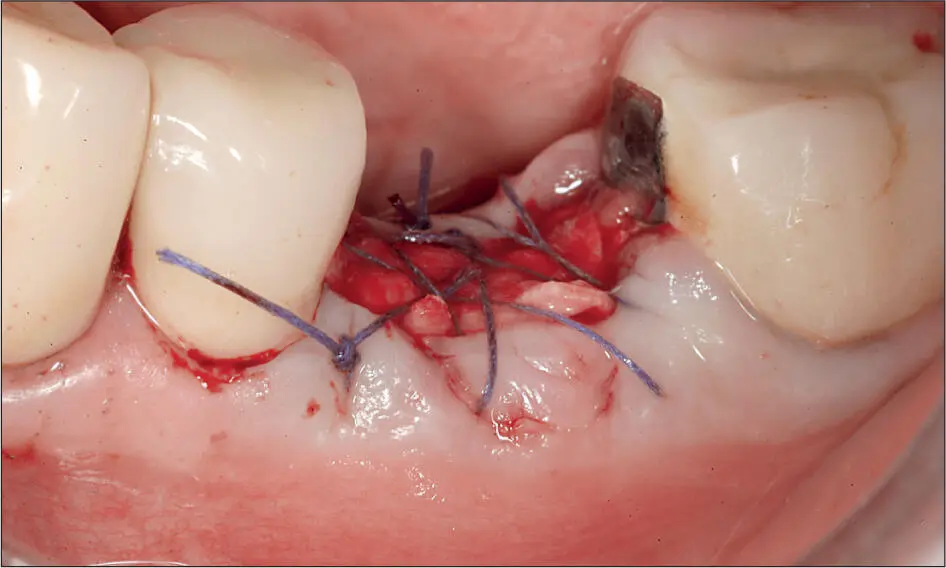

Abb. 3 c In die dekontaminierte Alveole wurde Knochenersatzgranulat in Form von entproteinisiertem bovinem Knochenmineral mit 10 % Kollagen (Bio-Oss Collagen; Geistlich, Wolhusen, Schweiz) gefüllt, mittels einer Kollagenmembran (Bio-Gide; Geistlich) doppellagig abgedeckt und mit resorbierbarem 4-0 Vicryl-Nahtmaterial (Ethicon; Johnson & Johnson International) fixiert.